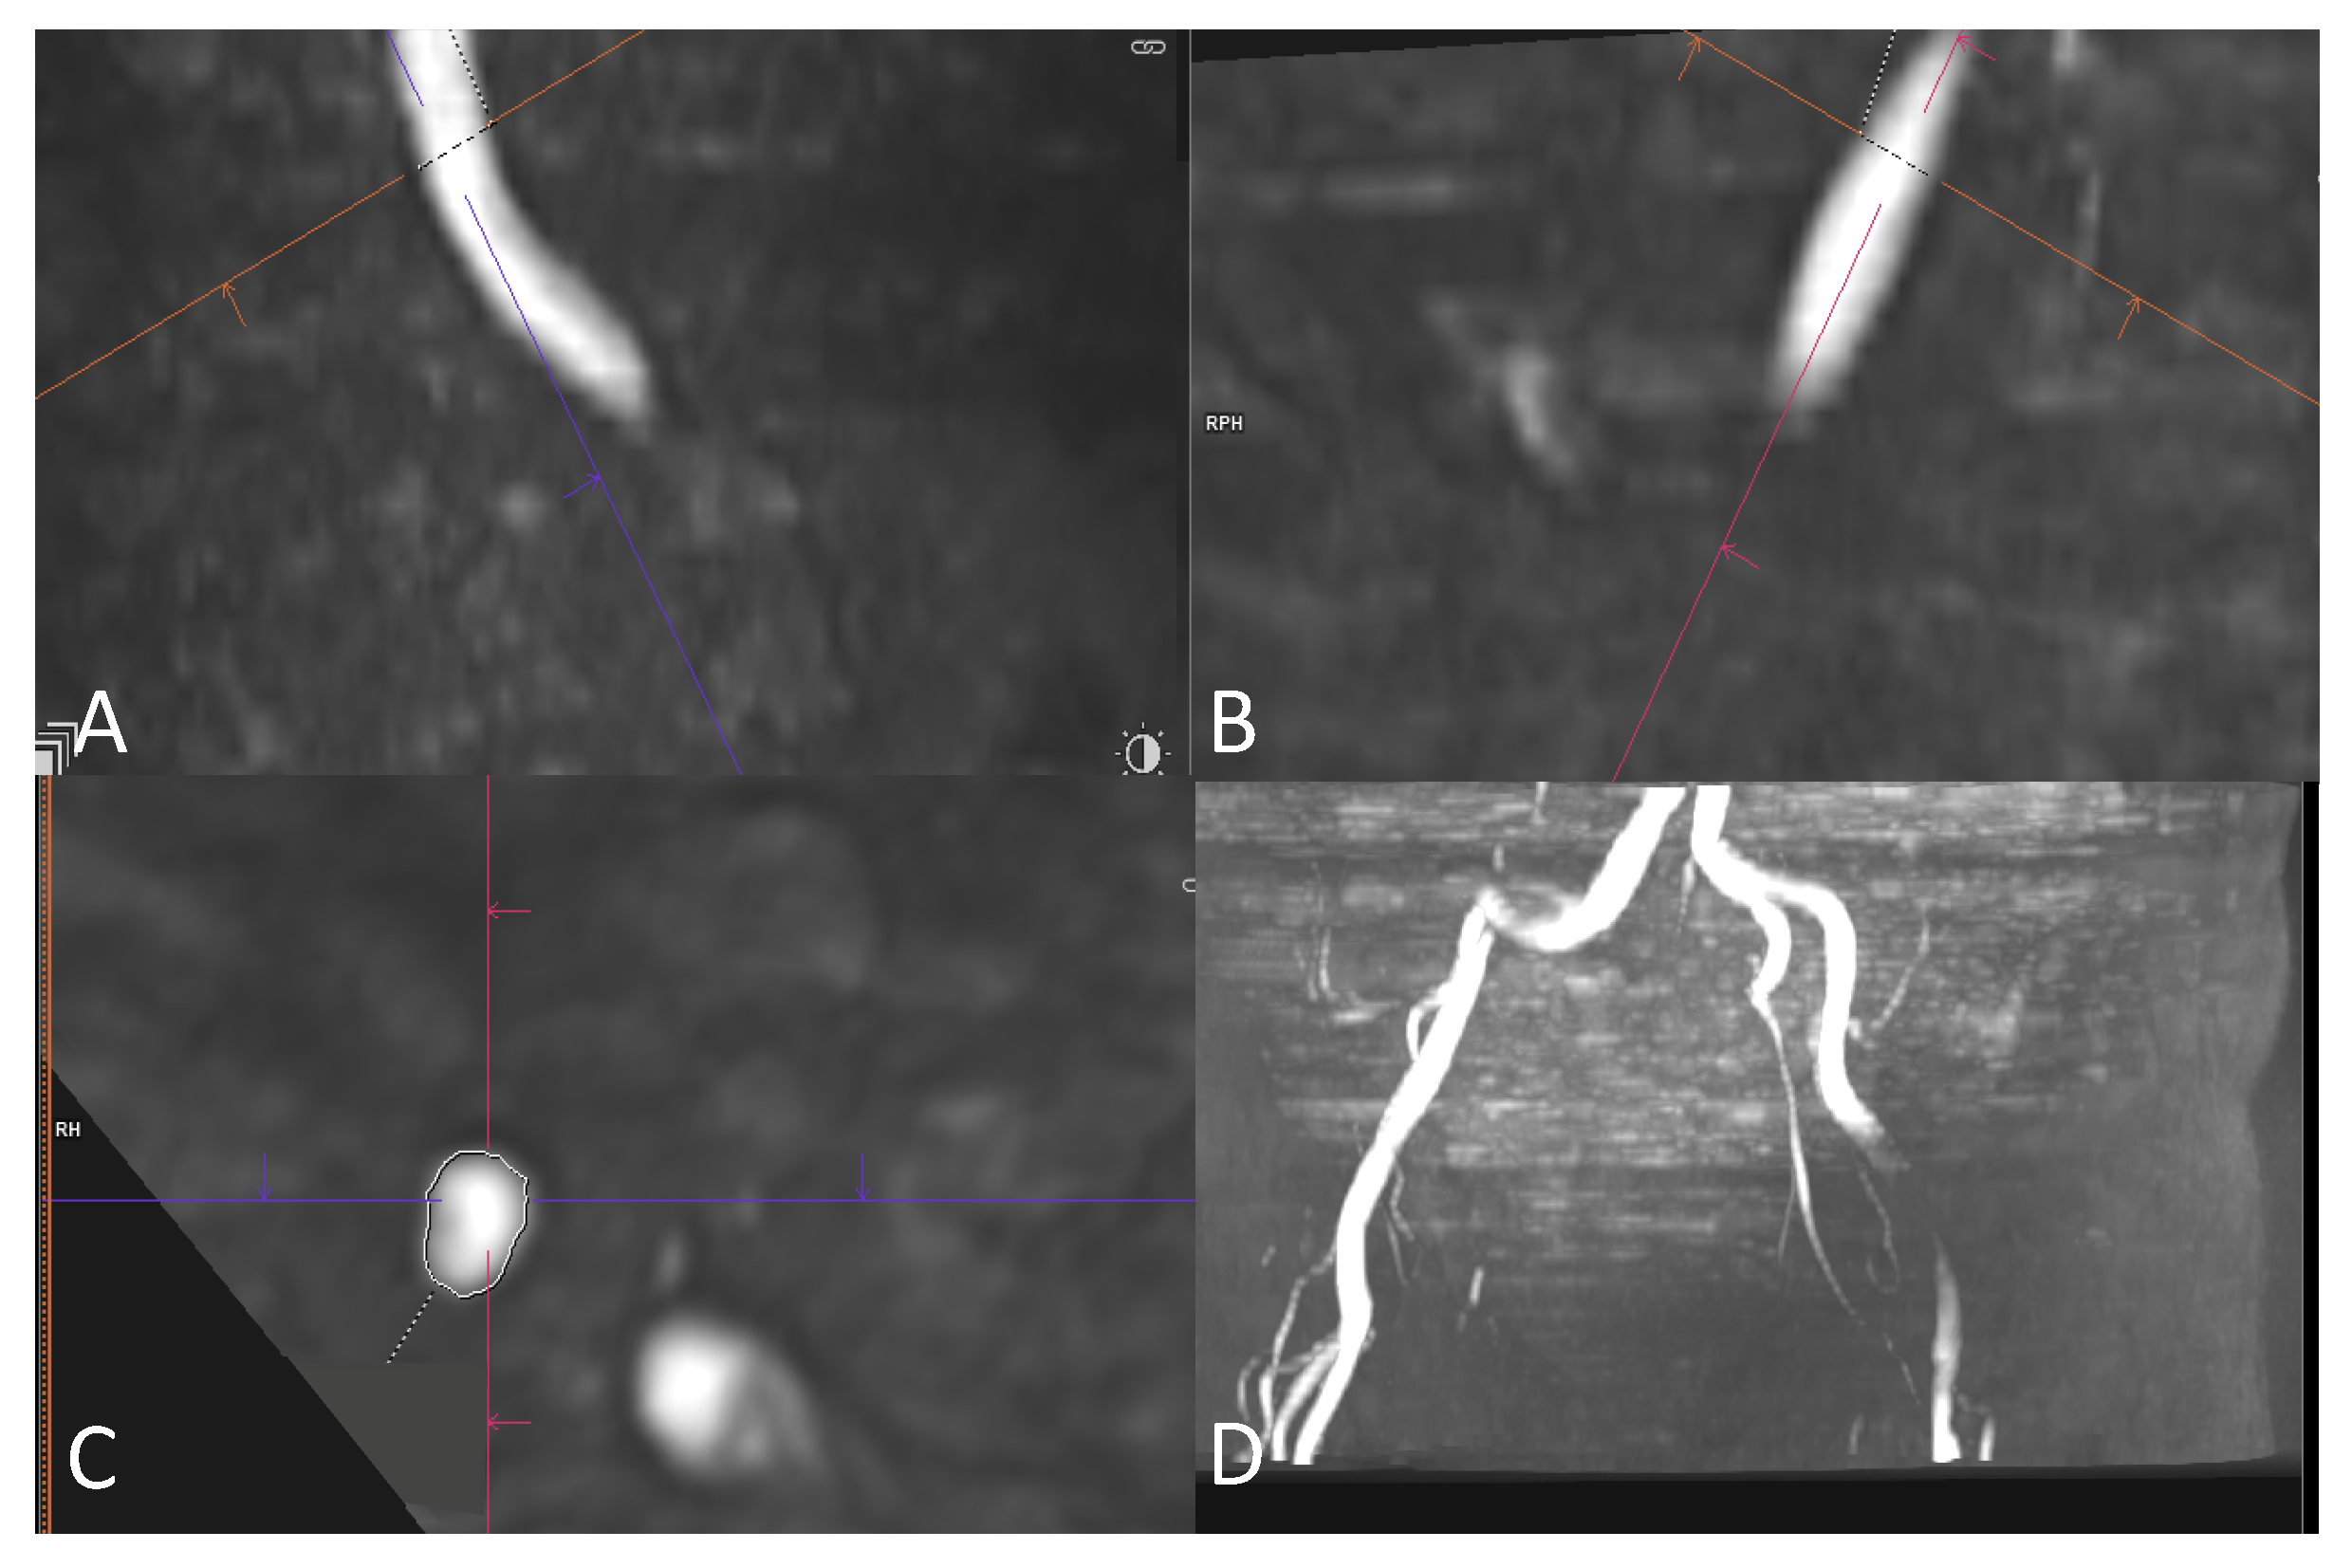

2.4. Image Review Methods

2.5. Assessment of the Access Route